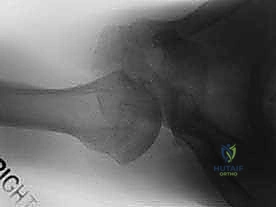

1. الأشعة السينية (X-rays): ضرورية جدًا. يصر الدكتور هطيف على طلب وضعيات خاصة (مثل Axillary view و Scapular Y view) لأن الوضعية الأمامية الخلفية العادية قد تبدو طبيعية تمامًا في حالات الخلع الخلفي (ما يُعرف بـ Lightbulb sign).

3. الأشعة المقطعية (CT Scan): تُطلب في حال وجود اشتباه بكسور في حافة التجويف الحقاني أو انخساف عظمي في رأس العضد (Reverse Hill-Sachs Lesion).